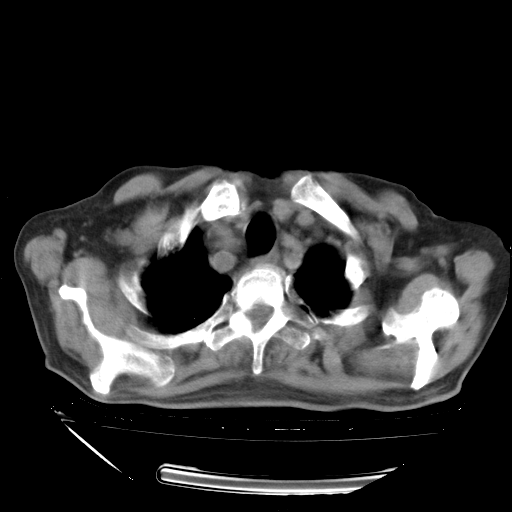

经过24天治疗,岳父的病情基本稳定。生活基本可以自理,可以下床活动。呼吸困难早已消失。体温基本正常。

只是甲强龙用80mg时血小板升到正常,改为60mg后又降到63×10*9/L。

主要治疗甲强龙80mg×14天,60mg×10天;同时抗结核(异烟肼+利福平+乙胺丁醇)。环磷酰胺0.1 tid 10天。

特别感谢胡教授、高管、桃子版主给出关键的治疗建议。桃版把所有肺部影像和全部临床资料请所在医院呼吸科、感染病科、结核科、临床免疫科专家会诊。临床免疫科专家制定了完整的治疗方案。